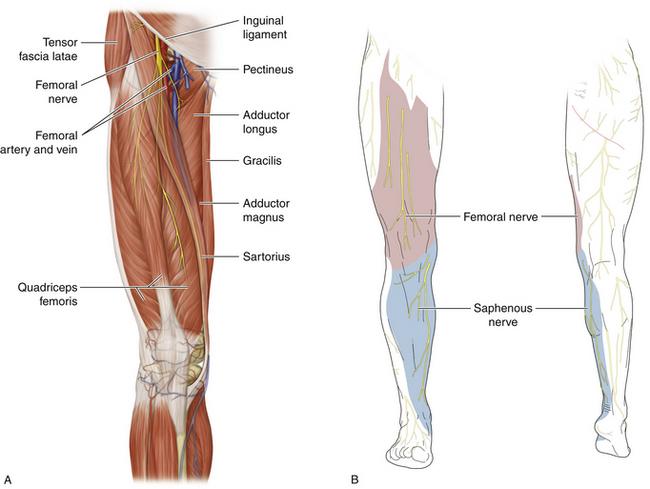

What is the path of the femoral nerve?

located superficial to iliacus

runs deep to inguinal ligament to enter anterior thigh

most lateral content of the femoral triangle

Which muscles are innervated by the femoral nerve?

all muscles of anterior thigh: sartorius, rectus femoris, vastus lateralis, vastus medialis, vastus intermedius

the iliacus

and half of pectinius

What nerve passes deep to the inguinal ligament to innervate the muscles of the anterior thigh? Obturator n. Sciatic n. Femoral n. Inferior gluteal n. Tibial n.

femoral n

Which of the following nerves is critical for leg extension? Femoral n. Obturator n. Tibial n. Common fibular n. Medial plantar n.

femoral n

origin course and distribution of saphenous nerve

spinal cord level

O femoral nerve

C descends with femoral vessels through femoral triangle and adductor canal then descends with great saphenous vein

D supplies skin on medial side of leg and foot

L3-L4

origin course and distribution of lateral femoral cutaneous nerve

O L2-L3

C emerges from the lateral border of the psoas major, crosses the iliacus muscle obliquely toward ASIS. Under the inguinal ligament, over sartorius muscle into the thigh, where it divides into an anterior and a posterior branch.

D lateral skin of thigh

origin and distribution of femoral nerve

O L2-L4

D iliacus, flexors of the hip and extensors of the knee